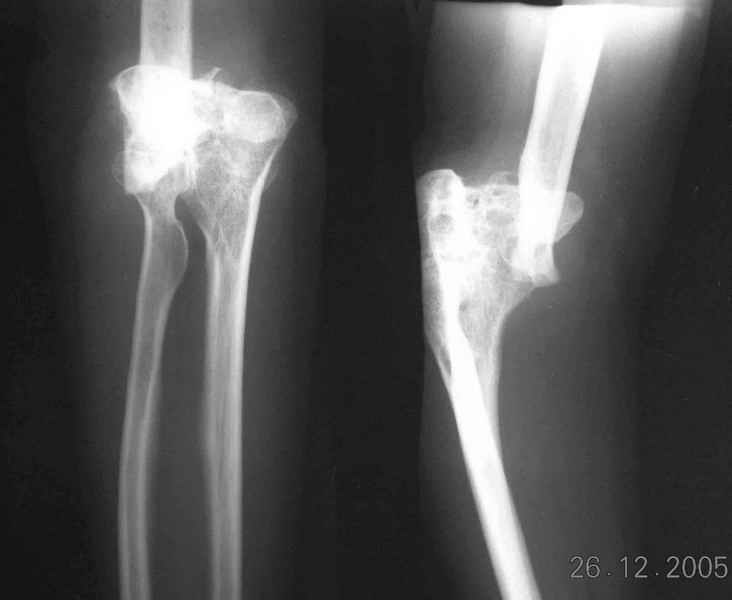

Re: Болтающийся ложный сустав дистального плеча

Уважаемый Ильдар, в ноябре 2005 г. мы оперировали практически полностью идентичную ситуацию у больного с гемофилией, поставили модифицированный

эндопротез локтевого сустава типа Сиваша с хорошим результатом. На заводе-производителе (в нашем случае - завод ЦИТО, но есть еще ООО

Эндосервис т/ф (095) 221-06-18, 500-41-30, 513-54-32 ) можно заказать протез этого типа по индивидуальным размерам для восполнения дефицита длины плечевой кости. Сейчас есть и более дорогие коммерческие эндопротезы фирмы Stryker. Наиболее активно оперируют локоть в ЦИТО, у нас тоже есть

собственный небольшой опыт эндопротезирования локтевого сустава.